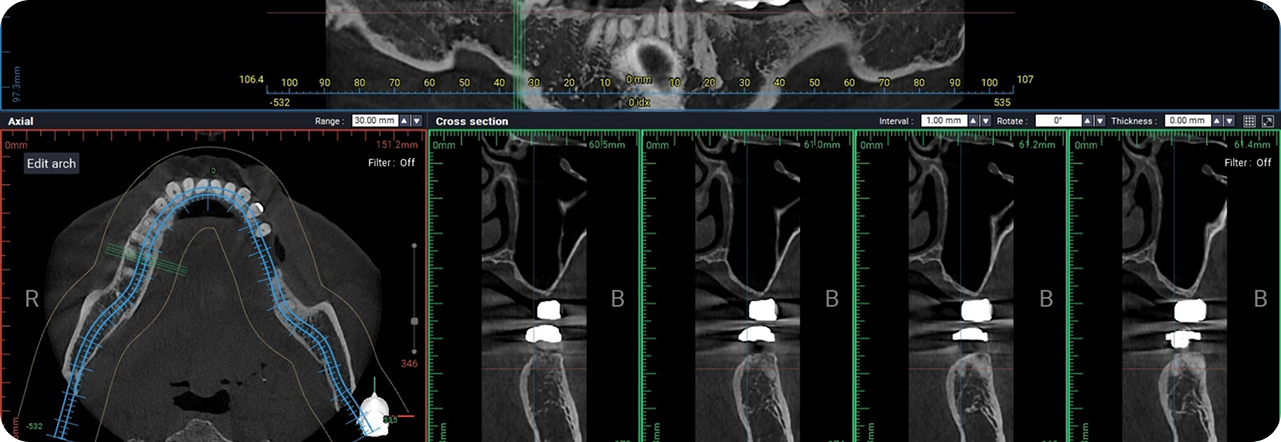

디지털 정밀 진단 기반

치료 설계

3D CT, 구강스캐너 등 정밀 진단 데이터를 기반으로

잇몸뼈 상태, 신경 위치, 교합 등, 환자 개개인의

해부학적 구조를 0.1mm 단위까지 파악하여,

안전하고 이상적인 치료 계획을 수립합니다.

3D-CT를 통한 정밀 진단

3D-CT 분석을 통해 상악동 구조와

골 상태를 정확하게 진단합니다.